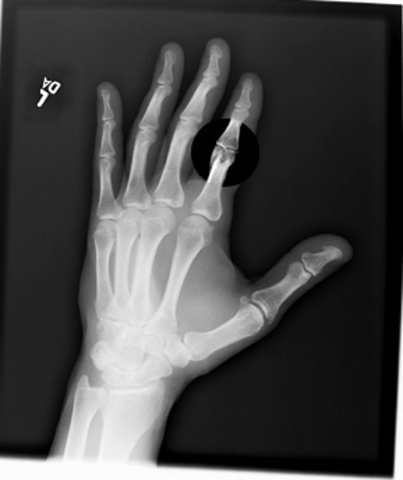

• Broke My Index Finger

Broke My Index Finger

Me and my brother were wrestling on our top bunk bed and we were getting out of control. We started to get really rough. He started to threaten to throw me off the top bunk if i didnt stop but i kept going anyways. I kept hitting him in the ribs and finally he got tired of me, he picked me up and through me off the bed. I flipped in mid-air and landed right on my index finger and it was broke. i couldnt stop crying, my mom took me to the hospital and i got a splint for it.